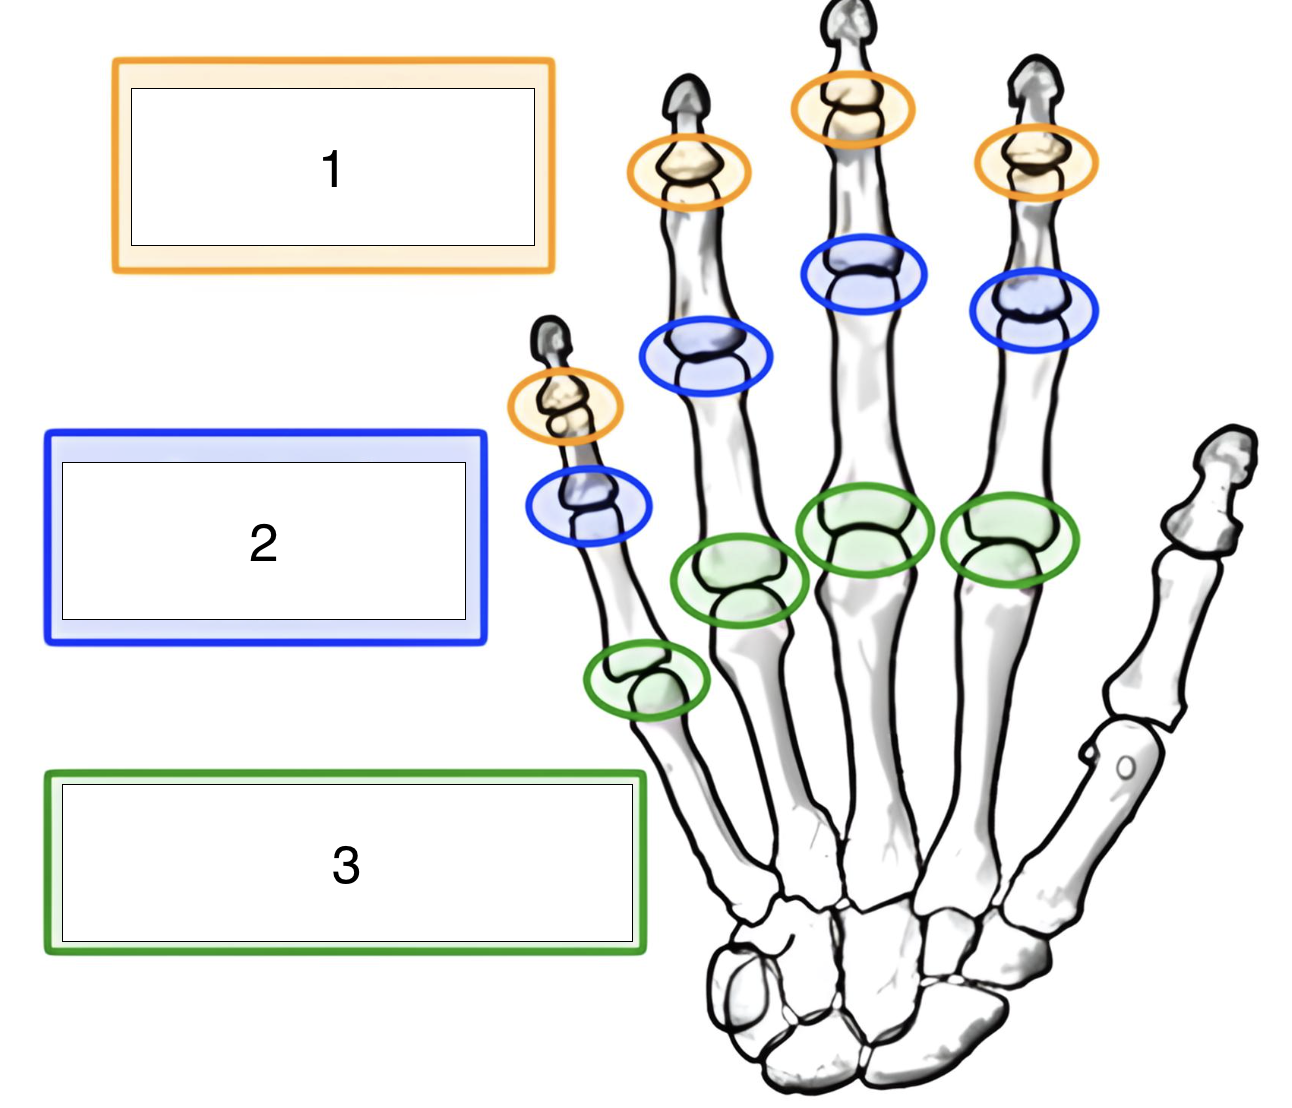

what is the highlighted joint (green, 3)?

metacarpophalangeal (MCP)

what is the highlighted joint (blue, 2)?

proximal interphalangeal (PIP)

what is the highlighted joint (orange, 1)?

distal interphalangeal (DIP)